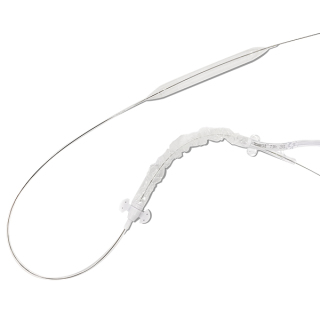

SuperFlow™ consists of a semi-compliant spiral balloon catheter (VesSpiral®) with a drug-coated Sirolimus surface.